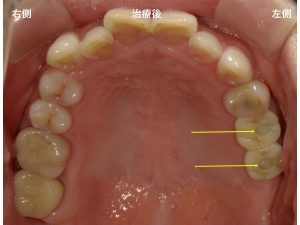

以下は、インプラント治療後です。

上顎左側の奥歯の素材は、

ジルコニアです。

ここで被せ物の噛む面に丸い白っぽい物があります。

以下の矢印部分です。

これは何かと言うと

ネジ式固定の被せ物です。

わかりにくいですよね。

簡単に言えば、

この丸い部分だけは、ジルコニアではなく、

レジンという樹脂が詰まっています。